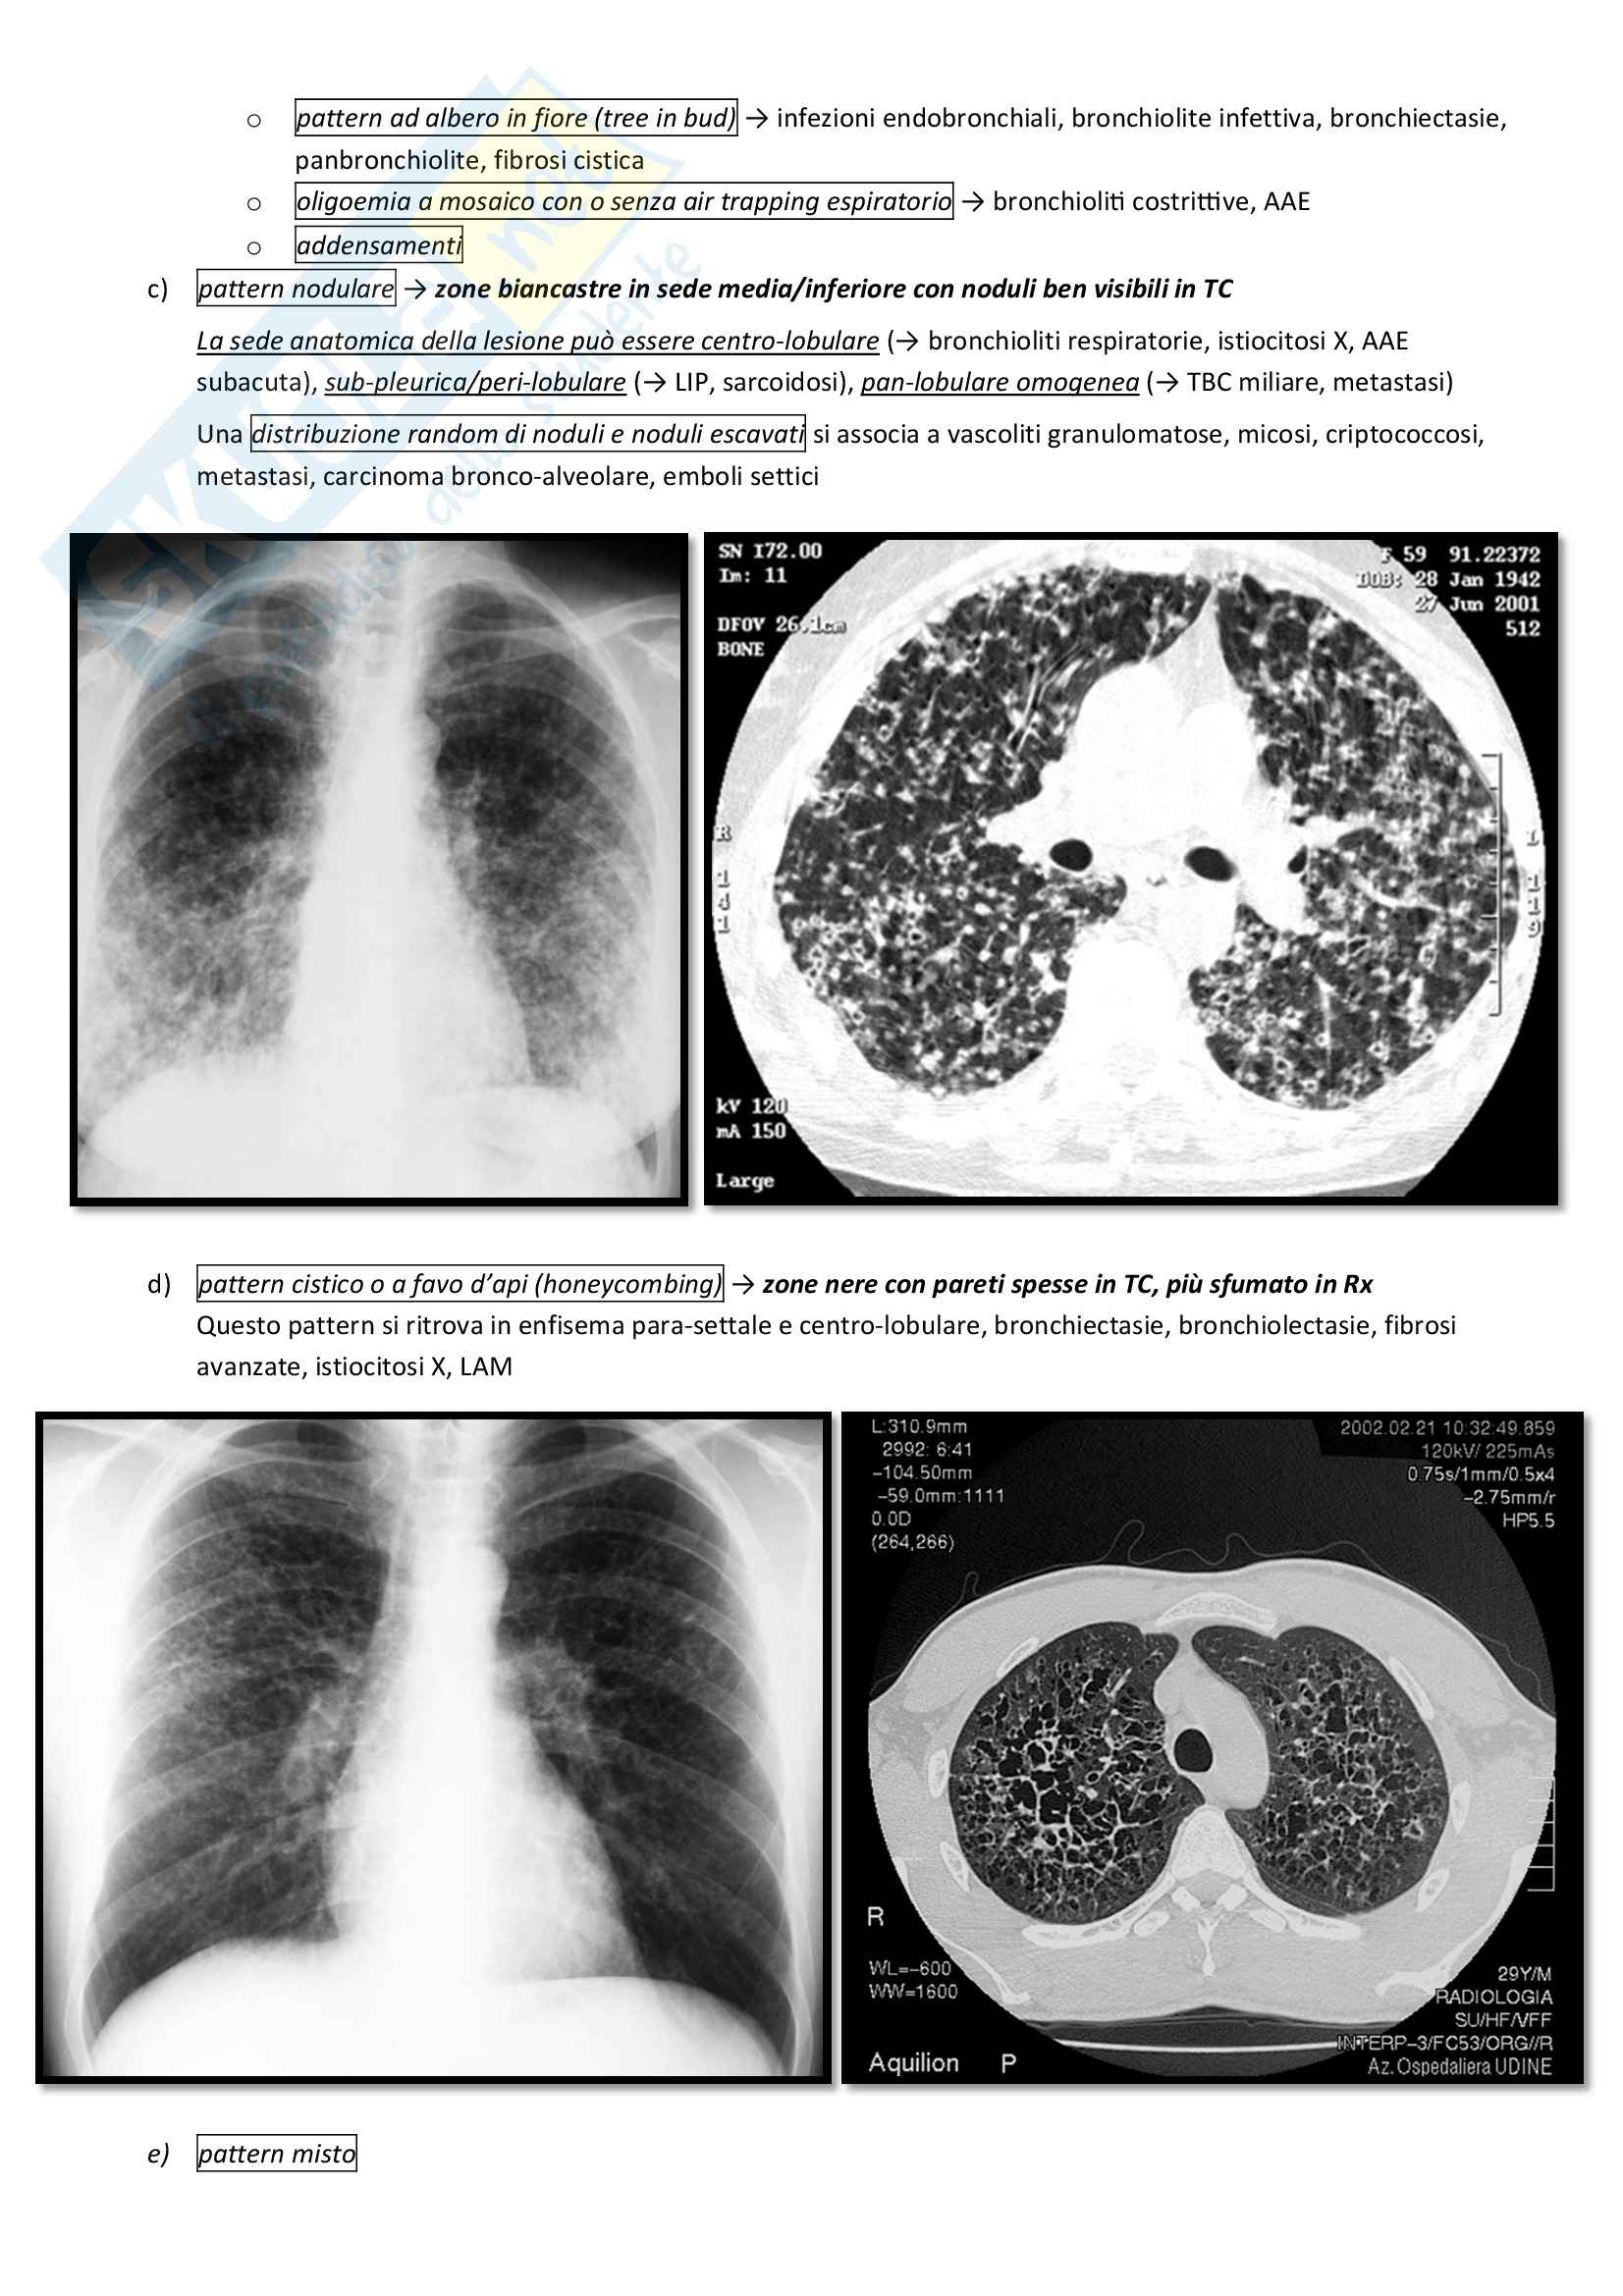

The skeleton is the most commonly involved organ system in Langerhans cell histiocytosis (LCH) and is by far the most common location for singlelesion LCH, often referred to as eosinophilic granuloma (EG) (the terms are used interchangeably in this article)For a general discussion of this disease please refer to the article on Langerhans cell histiocytosis (LCH). Ciao sono Sonia all'età di 5 anni mi sono stati diagnosticati 2 istiocitosi X, uno all'omero dx ed un altro al femore sx Ho fatto 2 anni di chemioterapia e fortunatamente sono guarita Oggi ho 29 anni faccio un lavoro dove il mio tempo lo passo all'impiedi e alzando pesi!. Download PDF Sorry, we are unable to provide the full text but you may find it at the following location(s) http//hdlhandlenet//15 (external link).

Xray small nodules generally up to 1 cm and variably sized cysts High resolution CT bronchiolocentric stellate nodules possibly with surrounding ground glass opacities, some with faint lucent cavity Advanced disease with cysts, emphysema adjacent to scarring, reticular and nodular opacities, honeycombing, can mimic IPF. Histiocitosis X (HX) represents a group of disorders due to proliferation of abnormal histiocytes exhibiting immunophenotypical and ultrastructural features similar to Langerhans cells HX can become manifest as an isolated lesion or may affect several organs at once.